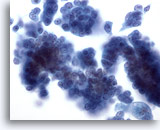

Figure 29

Breast FNA, Ductal carcinoma in situ.

Clusters of fairly bland tumor cells are noted. A vague impression of a fibrovascular core is noted in the cell group on the right. 40x

Figure 29

Breast FNA, Ductal carcinoma in situ.

Clusters of fairly bland tumor cells are noted. A vague impression of a fibrovascular core is noted in the cell group on the right.

40x